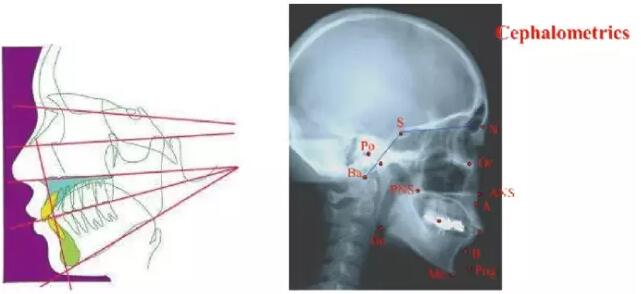

在咬合功能障碍的治疗中,需要考虑到的最重要的因素是合平面的倾斜度和垂直距离。通常是通过头影测量分析法来诊断的。Sato教授改进了“Denture-Frame-Analysis牙弓结构分析”用来定义合平面和颌面部骨骼之间的关系,这种分析方法很容易掌握。Sato教授还改进了MEAW (Multiloop-Edgewise-Arch-Wire)多曲方丝弓技术,该技术被证实可以成功地矫正牙齿的位置不良。为实现这一目的,在上颌MEAW弯制较小的后倾曲,在下颌MEAW弯制较大的后倾曲并使用短的II类弹性牵引。

●颅颌面系统的头影测量法

●头影测量功能分析